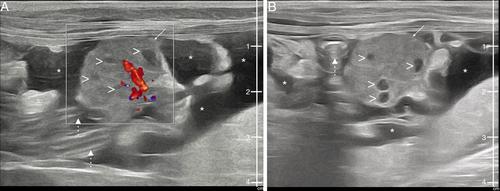

对一只4岁的雌性家短毛猫进行了为期3天的呼吸困难和嗜睡史评估。腹部超声和胸部x线片显示腹部和胸腔积液,以及两个子宫角和盆腔腹部圆形肿块。这两种积液都与富含蛋白质的修饰转体相容,传染病阴性。手术切除肿块和子宫,组织学显示卵巢正常循环和子宫腺增生。在术后两周的随访中,积液完全消失,猫完全康复。在人类医学中,Meigs综合征的特征是胸膜和腹腔积液三联征,并伴有卵巢肿块,最常见的是纤维瘤。这是一份报告,描述了一只患有卵巢残余组织的年轻猫的梅格斯样综合征。

A 4-year-old spayed female domestic shorthair cat was evaluated for a three-day history of dyspnea and lethargy. Abdominal ultrasonography and thoracic radiographs revealed the presence of abdominal and pleural effusions, along with both uterine horns and a rounded mass in the pelvic abdomen. Both effusions were compatible with modified transudates rich in protein and negative for infectious disease. The mass and uterus were surgically removed, and histology revealed a normal cycling ovary and uterine glandular hyperplasia. At the two-week follow-up after surgery, the effusion had completely disappeared, and the cat had fully recovered. In human medicine, Meigs' syndrome is characterized by the triad of pleural and abdominal effusions along with ovarian mass, most commonly fibromas. This is a report describing a Meigs' like syndrome in a young cat with ovarian remnant tissue.